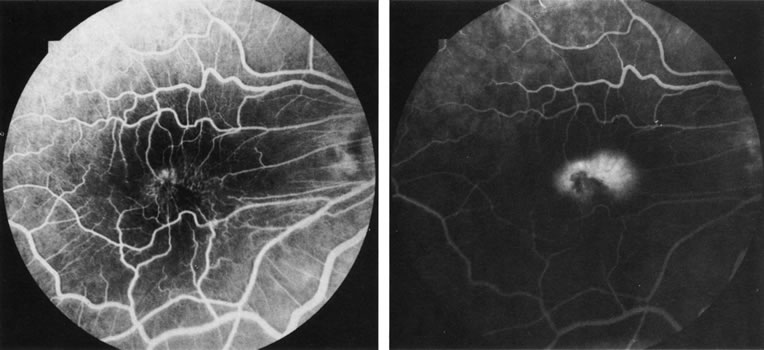

FA is also useful in characterizing two other subgroups of CNV: retinal angiomatous proliferation (RAP)8–16 and polypoidal choroidal vasculopathy (PCV).17–50 RAP begins in the deep retinal complex, forming intraretinal neovascularization (IRN), which may subsequently progress to extend beneath the neurosensory retina, forming subretinal neovascularization (SRN), and a vascularized PED.8 In the later phases of the process there may be a retinal-choroidal anastomosis (RCA). Clinical features of RAP include intraretinal hemorrhages, cystoid macular edema, and associated vascularized PED. FA is useful in revealing the presence of the angiomatous intraretinal vascular complex and the extension of the associated PED (Figs. 12 and 13). However, other diagnostic techniques such as indocyanine green (ICG) angiography, and optical coherence tomography (OCT) may be able to better demonstrate the presence of the RAP lesion.

Fig. 12. A. Clinical photograph of a retinal angiomatous proliferation (RAP) lesion (arrow). Note the intraretinal angiomatous proliferation, a feeding retinal arteriole, and a draining retinal venule, as well as the presence of intraretinal hemorrhages. B–C. Fluorescein angiography reveals late leakage from the RAP lesion.